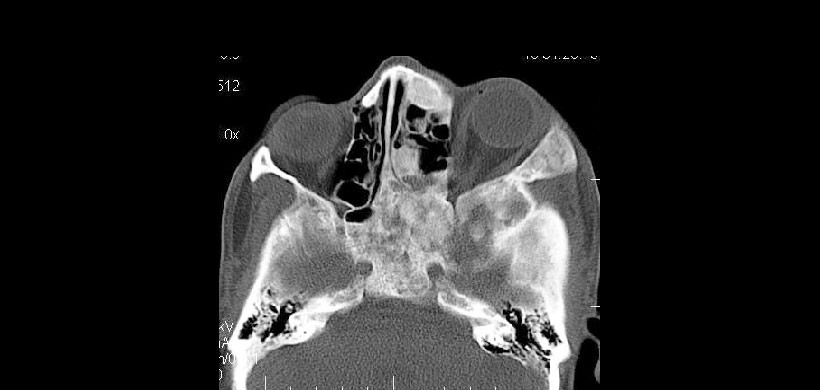

Figura 10: Corte axial de TC que muestra la afectación del seno maxilar derecho. Además, el arco zigomático, el cigoma, la base del cráneo, el proceso mastoideo, las placas pterigoides y el esfenoides del lado derecho también estuvieron involucrados. Hubo evidencia de participación de cóndilos occipitales de ambos lados y del clivus.